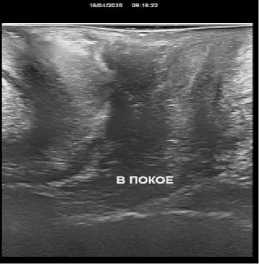

По результатам проведенных контрольных УЗ исследований нами было установлено, что при трансректальном исследовании толщина ректовагинальной перегородки увеличилась в среднем с 1,1+/–0,2 см до 1,5+/–0,2 см. Перегородка со стороны прямой кишки обрела четкие контуры за счет уменьшения ее складчатости. Произошло уменьшение диастаза бульбокавернозных мышц с 0,9+/–0,2 см до 0,3+/–0,1 см. При трансперинеальном УЗИ уменьшилась толщина перегородки за счет снижения ее складчатости и регрессировал пролапс перегородки в сторону влагалища при натуживании пациенток (рис. 1).

До операции

После операции

До операции После операции

Рис. 1. УЗИ картина до и после операции

Fig. 1. Ultrasound picture before and after surgery